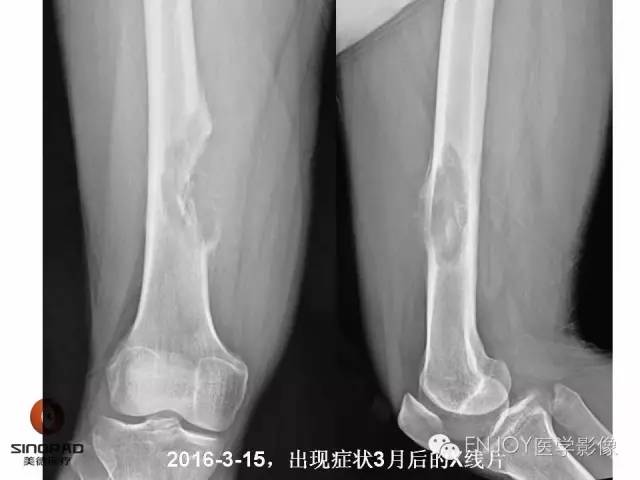

1、病灶的定性诊断是?(单选)

A:良性肿瘤

B:恶性肿瘤

C:非肿瘤

2、你的诊断(单选)

骨肉瘤(传统型)

骨肉瘤(毛细血管扩张型)

多形性肉瘤(以往称为:恶性纤维组织细胞瘤)

软骨肉瘤(2-3级)

转移瘤